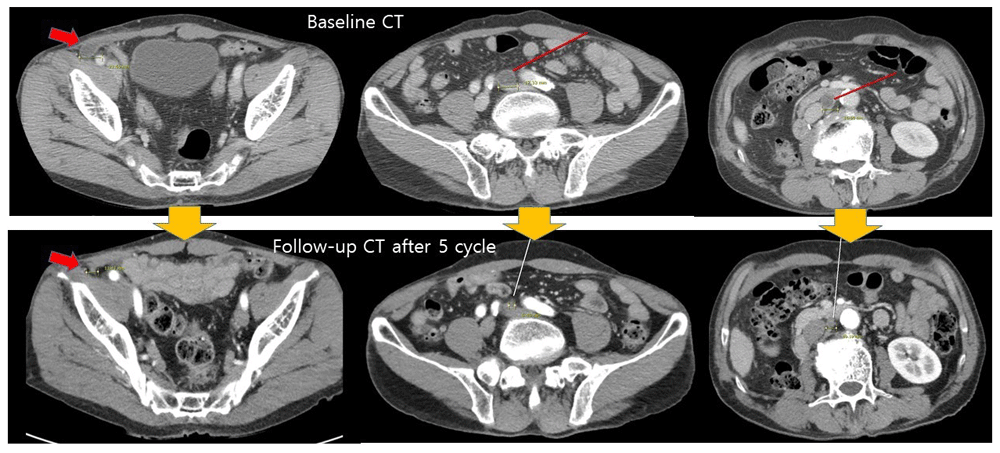

The patient was discharged within 10 days without any complication including azotemia and resumed the two-week proton therapy for esophageal cancer. On the postoperative one-month follow-up CT scan, an increased size and necrosis of aortocaval lymph nodes and multiple metastatic lung nodules were detected. Three cycles of adjuvant gemcitabine and carboplatin (gemcitabine 1000mg/m2 D1, 8, and carboplatin AUC 5 D1, every 3 weeks) chemotherapy was administered due to the decreased renal function because of an underlying chronic kidney disease. The follow-up imaging after 3 cycles (9 weeks) of the initial treatment regimen indicated disease progression; thus, a second-line systemic therapy was initiated using an immune checkpoint inhibitor, atezolizumab (1200mg, every 3 weeks). After three cycles of atezolizumab, the multiple enlarged lymph nodes and lung nodules were no longer enlarged, and after five cycles of atezolizumab the overall size of multiple metastatic lesions decreased (Figure 3), indicating a partial response to atezolizumab. The patient has undergone seven cycles of atezolizumab without any grade 3 adverse event, and will continue to be treated.